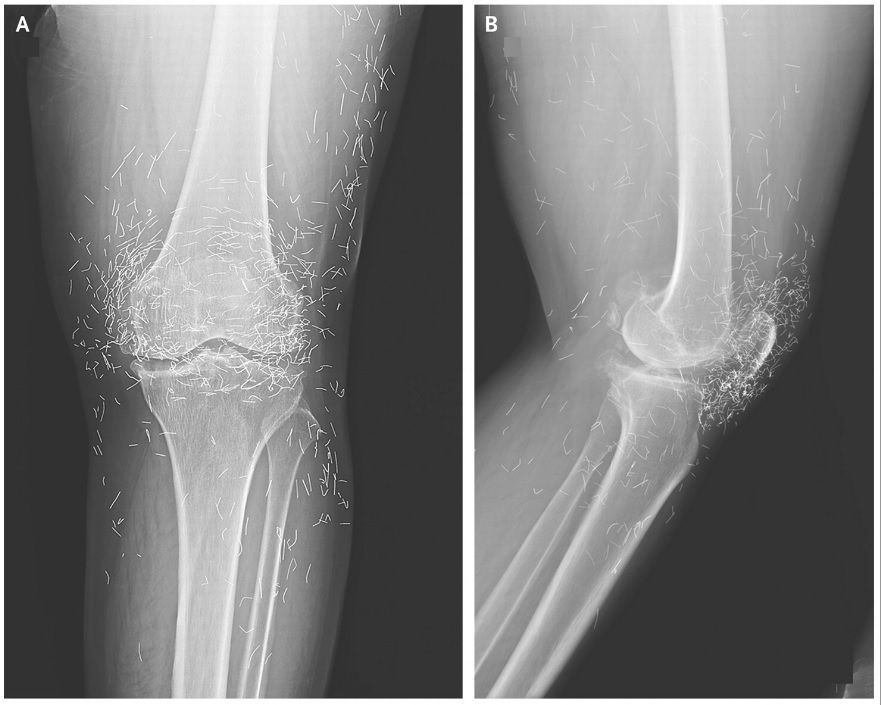

Doctors discovered a gold mine in an X-ray image of a woman's knees who was suffering from acute joint pain: hundreds of small gold acupuncture needles left in her tissue. Osteoarthritis is a disorder in which the cartilage and bones in the joints deteriorate, producing pain and stiffness. The 65-year-old South Korean lady had previously been diagnosed with it. She had resorted to acupuncture when pain killers and anti-inflammatory medications failed to cure the pain in her knees and instead produced stomach trouble, she informed her doctors. Her physicians reported in the New England Journal of Medicine in December 2013 that the needles, which were probably composed of gold, were purposely left in her tissue for ongoing stimulation.